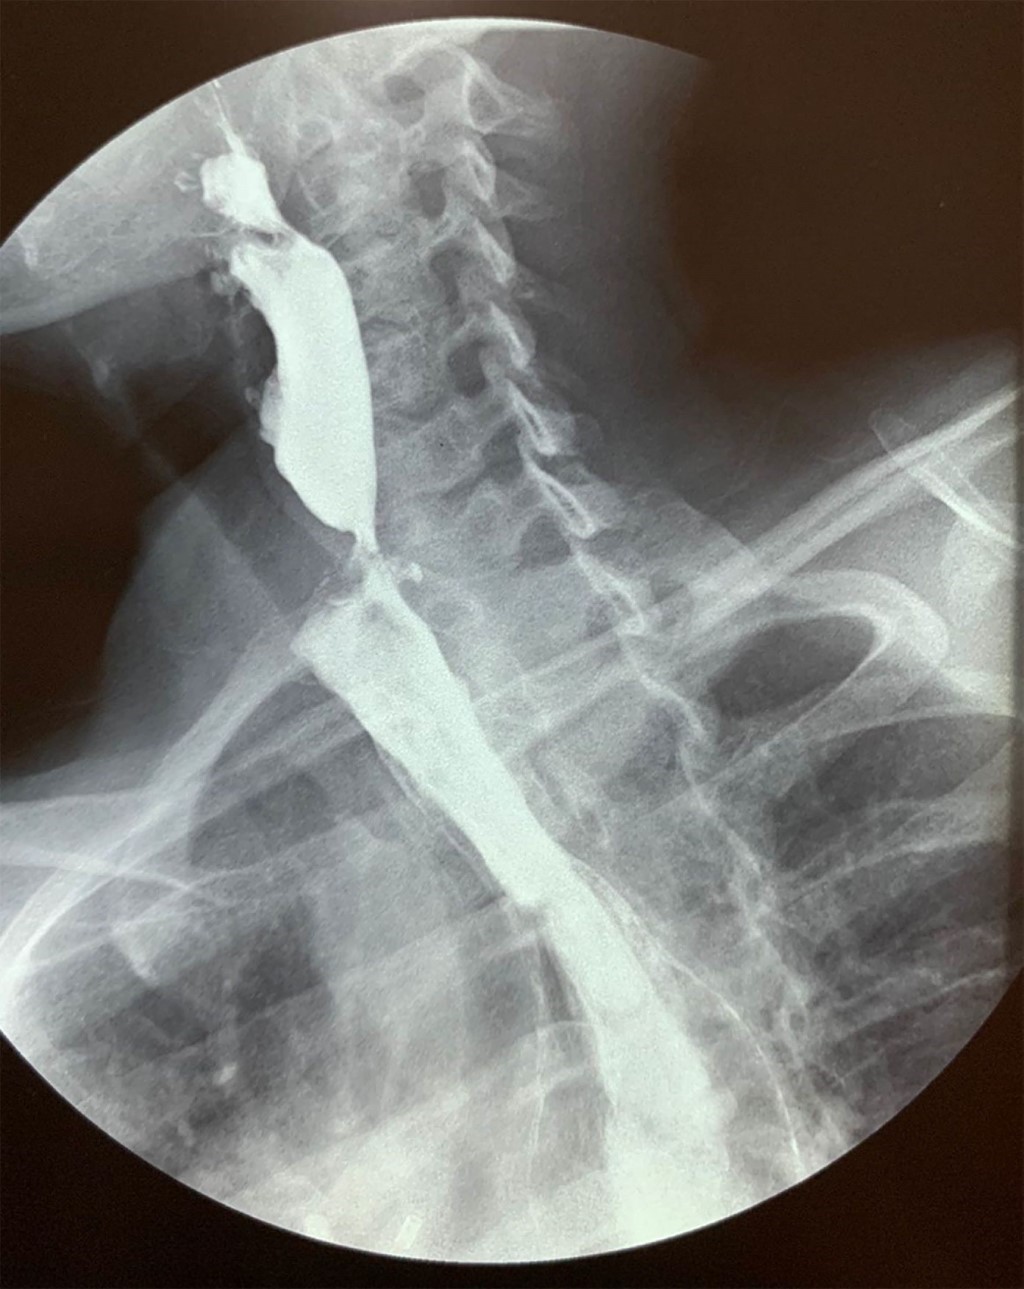

Se efectúa endoscopia en la cual se reporta estenosis esofágica a 18 cm de la arcada dentaria, imposibilitando el paso del endoscopio, sin poder realizar dilatación y sin ser clasificable debido a la estenosis tan importante que presenta el paciente. Se realiza serie esofagogastroduodenal con medio de contraste baritado que muestra estenosis esofágica con paso filiforme del medio de contraste a nivel del tercio medio del esófago (Figuras 1 y 2). Se hace yeyunostomía un mes previo a tratamiento quirúrgico definitivo, con mejoría de condiciones generales y estado nutricional preoperatorio.

Figura 1

Figura 2